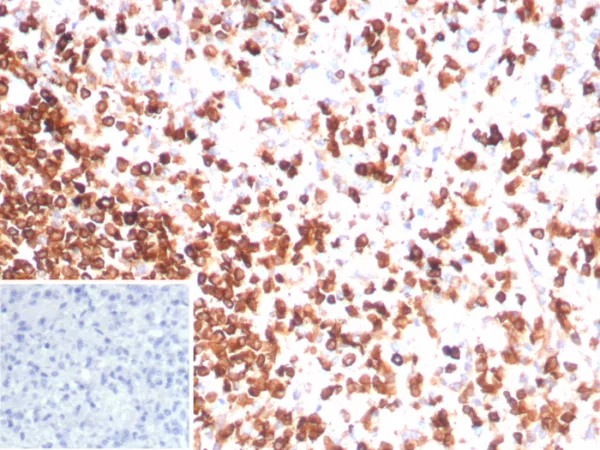

Formalin-fixed, paraffin-embedded human spleen stained with CD3e Recombinant Mouse Monoclonal Antibody (rC3e/8881). Inset: PBS instead of primary antibody; secondary only negative control.

Recognizes the epsilon-chain of CD3, which consists of five different polypeptide chains (designated as gamma, delta, epsilon, zeta, and eta) with MW ranging from 16-28kDa. The CD3 complex is closely associated at the lymphocyte cell surface with the T cell antigen receptor (TCR). Reportedly, CD3 complex is involved in signal transduction to the T cell interior following antigen recognition. The CD3 antigen is first detectable in early thymocytes and probably represents one of the earliest signs of commitment to the T cell lineage. In cortical thymocytes, CD3 is predominantly intra-cytoplasmic. However, in medullary thymocytes, it appears on the T cell surface. CD3 antigen is a highly specific marker for T cells, and is present in majority of T cell neoplasms.